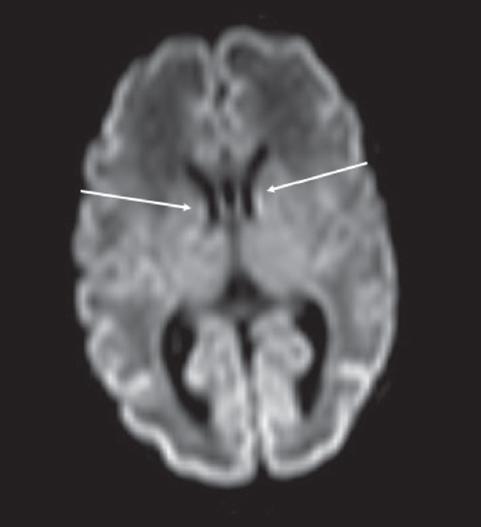

Методы и материал. Выполнено исследование паттерна нейропластичности — регрессии герминального матрикса у недоношенных новорожденных с экстремально низкой массой тела (ЭНМТ) при рождении методами краниальной сонографии (КСГ) и магнитно-резонансной томографии (МРТ). Был обследован 21 недоношенный новорожденный с ЭНМТ без нейровизуализационных признаков повреждения герминального матрикса, в первую очередь кровоизлияния из герминального матрикса. Проведено измерение герминального матрикса передних отделов боковых желудочков головного мозга у исследуемых детей методом КСГ. Выполнено МРТ головного мозга 15 недоношенным детям группы исследования в постконцептуальном возрасте (ПКВ) 27–38 недель с использованием традиционных импульсных последовательностей и дополнительно DWI — диффузионно-взвешенных изображений в стандартных проекциях. Также выполнено патоморфологическое исследование герминального матрикса в области передних отделов боковых желудочков у трех умерших детей из группы исследования.

Результаты и выводы. Выявлена регрессия герминального матрикса у недоношенных новорожденных с полной редукцией к 30 неделям ПКВ по результатам КСГ. Применение DWI ВИ позволило выявить герминальный матрикс у недоношенных детей до 34 недель ПКВ, тогда как при помощи других импульсных последовательностей удается визуализировать герминальный матрикс до 32 недель ПКВ.